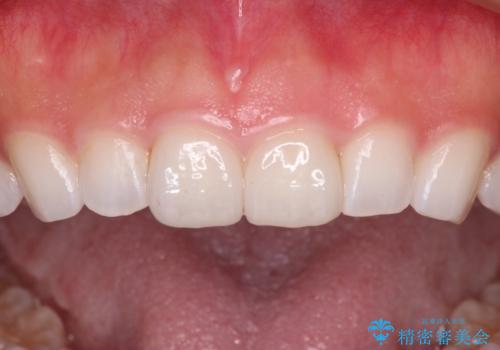

むし歯はなく、矯正治療で咬み合わせが改善していたので、侵襲量の少ないラミネートベニアにて治療することとしました。

ラミネートベニアは切削量が少ないことがメリットとしてあげられますが、色調を周辺と合わせられないこと、接着境界線が長く汚れや歯石が溜まりやすいことがデメリットとして考えられます。

また、接着境界線にむし歯がある場合には適用外となるなど、適用症例を選ぶため、治療に際して担当医としっかりと相談することが大切です。